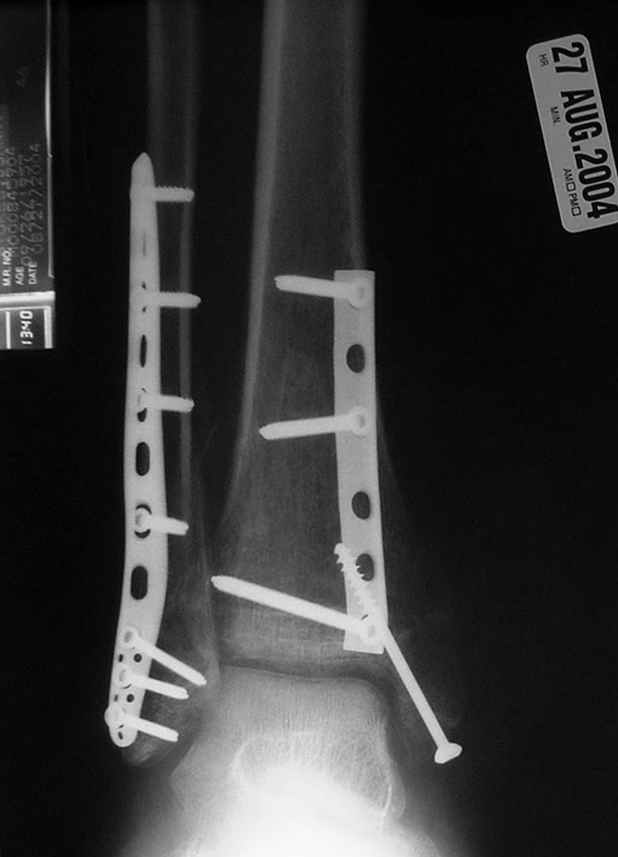

Отправитель: Djoldas Kuldjanov, M.D. 16 Сентябрь 2004, 22:00

Второй случай сделан из одного разреза

Дж

ЕЧ LISS plate, mininvasive approach - luxurous !

На прямой проекции послеоперационного Рг макроскопически все выглядит очень анатомично, при микроскопическом ( :-)) ) рассмотрении можно все-таки заметить вальгизацию тарана, суставная щель в латеральном отделе сустава несколько уже , чем в медиальном при отсутствии латерального смещения тарана. У меня был аналогичный случай (без LISS , без мини доступа) с вальгусным наклоном тарана при восстановленном ankle mortise при последовательном наблюдении с интервалами в 6-8 недель в послеоперационном периоде отмечалось прогрессирующее сужение суставной щели в латеральном отделе сустава, закончившееся посттравматическим ОА, к счастью боли умеренные, купируемые аналгетиками или своими эндорфинами:-))(активная пациентка, у которой нет времени на болезни....) Какова жизненная ситуация в приведенном вами случае? И последнее, что я хотел бы прояснить для себя - фиксация внутренней лодыжки: я обычно комбинирую фиксацию компрессирующим винтом со спицей - по идее ротационная стабильность должна быть лучше, чем один винт, каковы ваши наблюдения в этом плане?

Pilon fracture:

-Появляется ориентир и остов, на чем можно строить восстановление, почему сперва малоберцовую, впервые обьяснили и описали (Pylon type and Ankle fractures) в середине 50х Rienau и Gay.

Восстановливая длину и ротацию малоберцовой кости, затем относительно легче произвести реставрацию остальных элементов перелома дистального эпиметафиза болшеберцовой кости.

конец малоберцевой кости, к нему прикрепляется латеральный суставной фрагмент дистального эпиметафиза большеберцовой кости (как на снимке)

и таранная кость, которые при репозиции малоберцовой кости репонируются автоматически.

-Малоберцовую! Можно низвести аппаратом или пластиной.